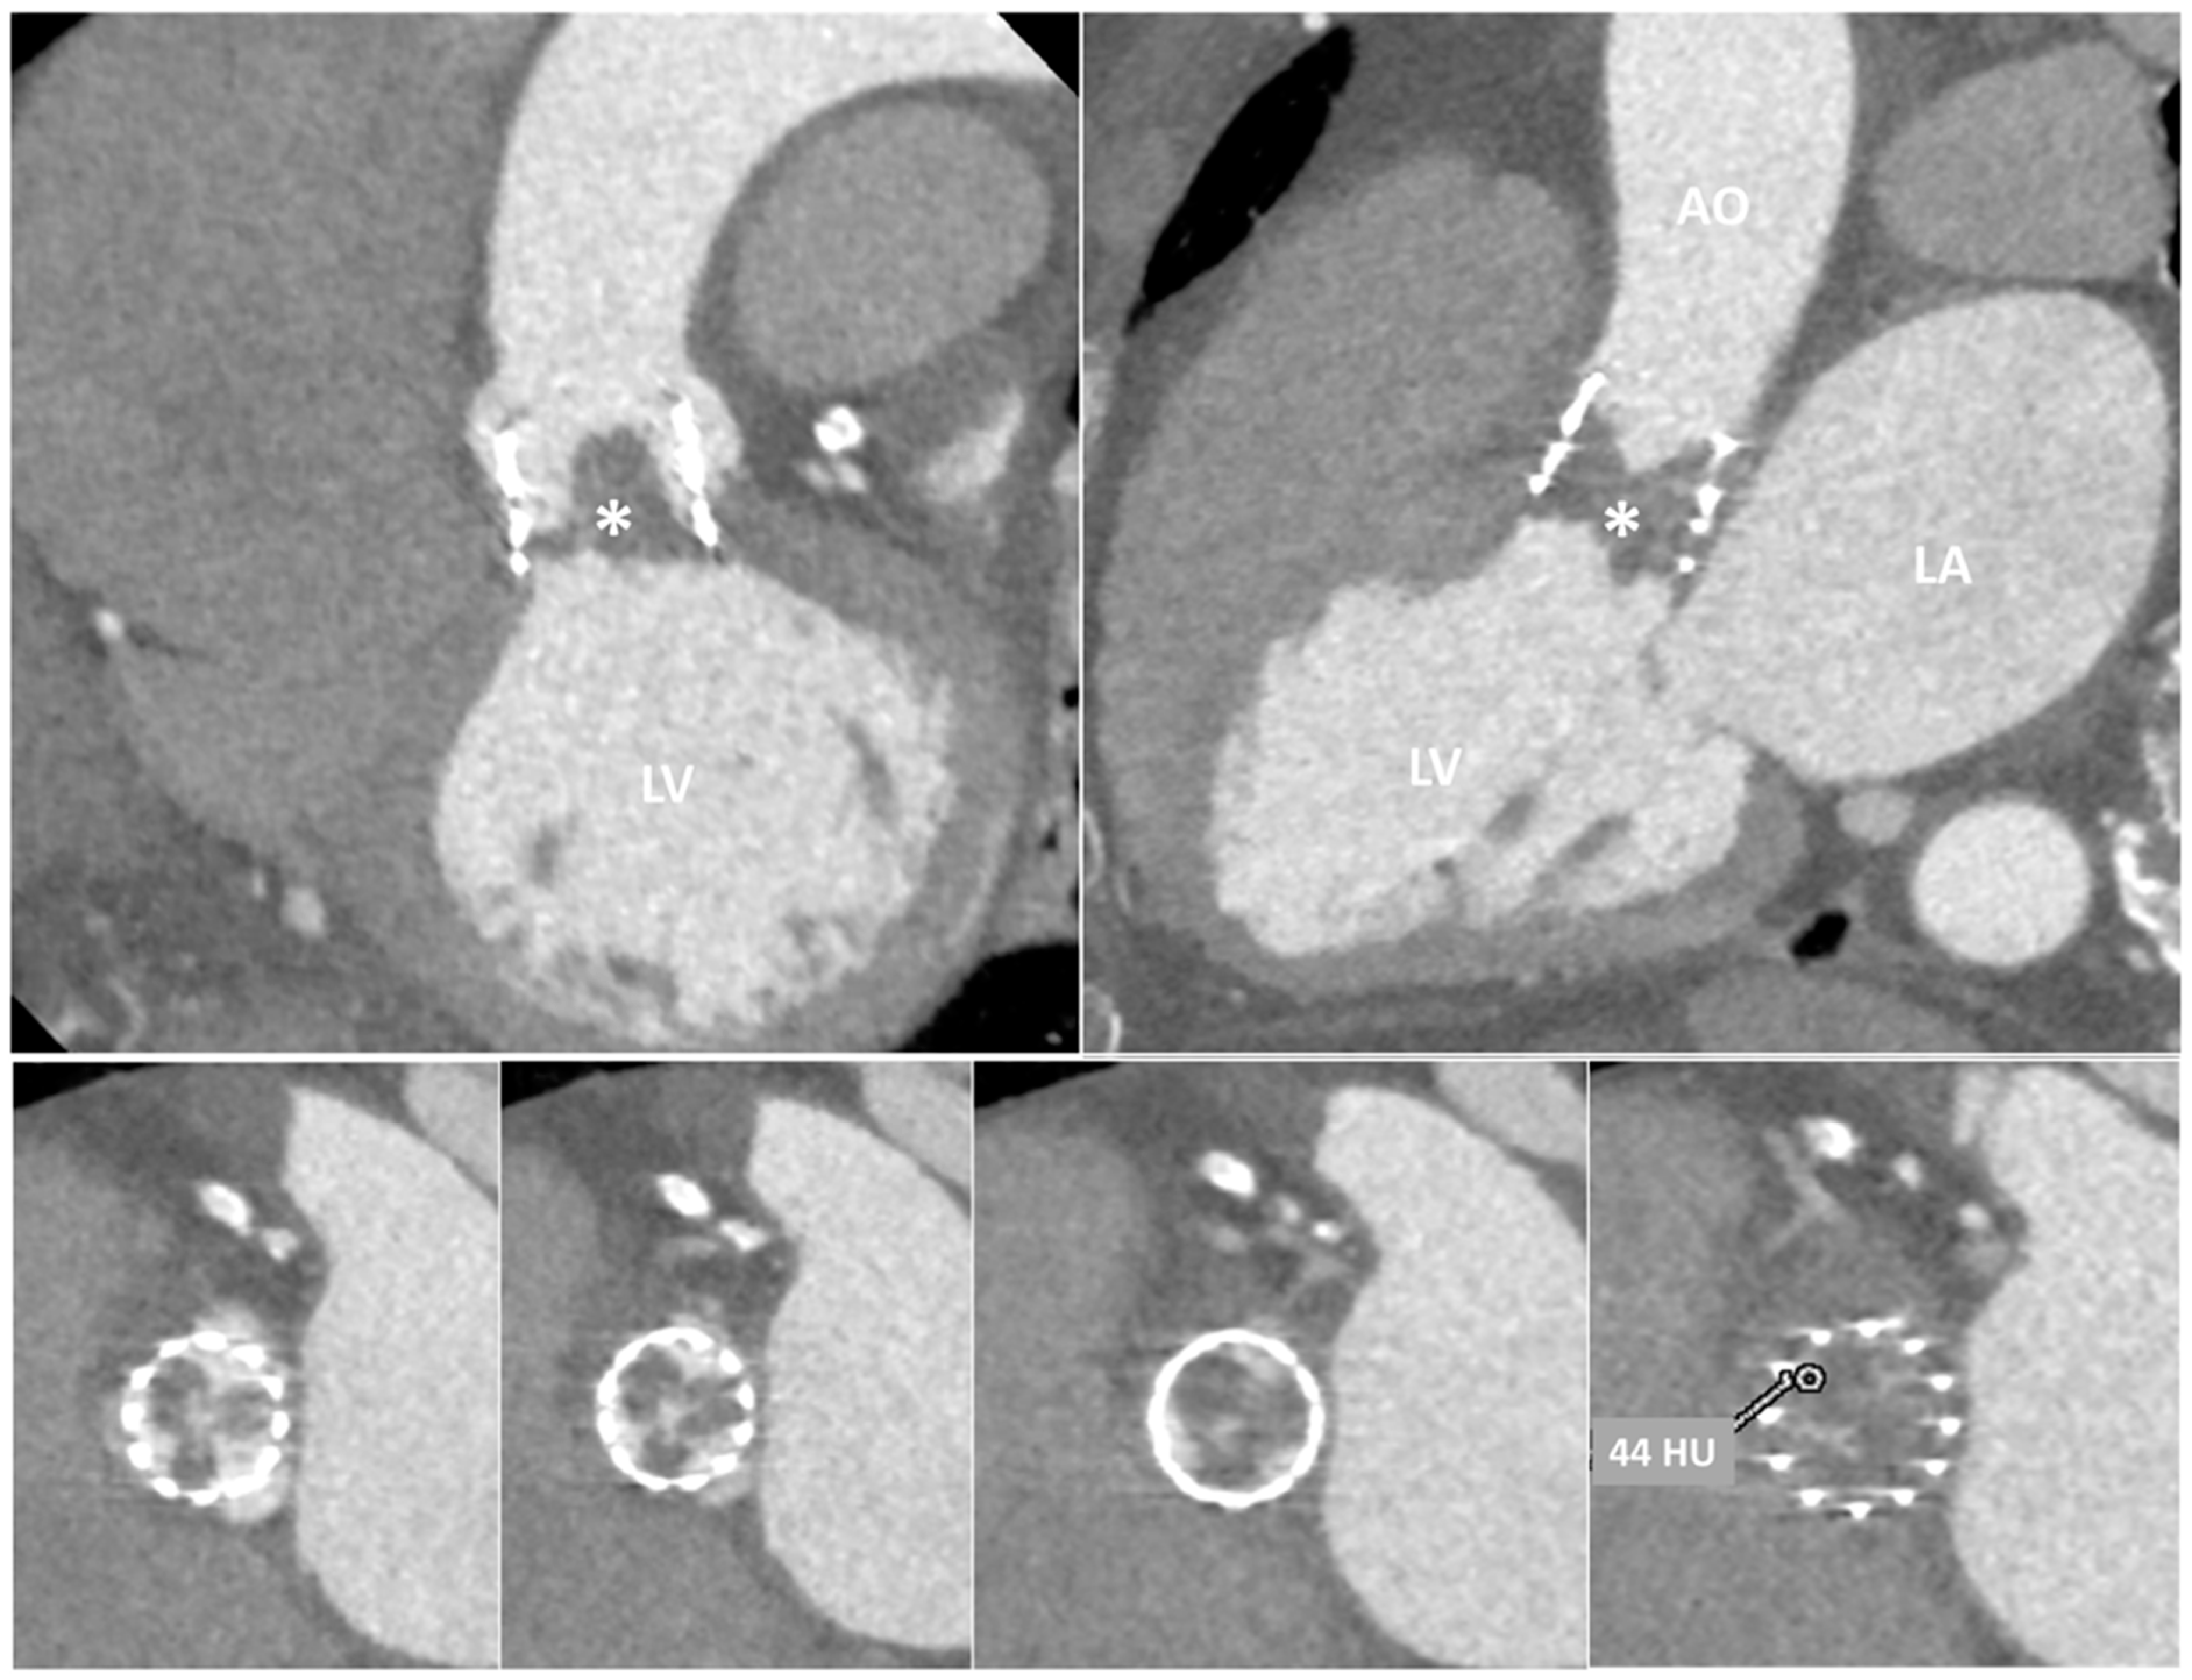

| TTE, TEE | Leaflet and/or ring thickening with diffuse or focal hyperechogenicity (calcifications). Reduced leaflet mobility. Leaflets’ fenestration, avulsion, or perforation. Stenosis or regurgitation. | Iso-hypoechogenic mass adherent to leaflets and ring, with leaflet thickening. Normal or reduced cusp mobility. More often, stenosis; regurgitation is uncommon. | Vegetations, diffuse or focal leaflets thickening, cusps perforation, wear or tear or cusp avulsion. Vegetation motion independent to cusps motion. Paravalvular complications: abscess, pseudo-aneurysm, fistula or dehiscence (and in some cases valve rocking) |

| CCT | Pannus (hypodense): HU ≥ 145; semicircular or circular structure located along leaflets’ surface or stent. Hyperdense leaflet thickening with or without calcifications, along with or without reduced mobility. | No calcifications. HU < 145. Hypoattenuated leaflet thickening (HALT), affecting (HAM) or reducing (RLM) leaflet motion. In some cases, large hypoattenuated mass. | Hypoattenuated mass adherent to leaflets or stent. Paravalvular complications: abscess, pseudo-aneurysm, fistula, or dehiscence. |